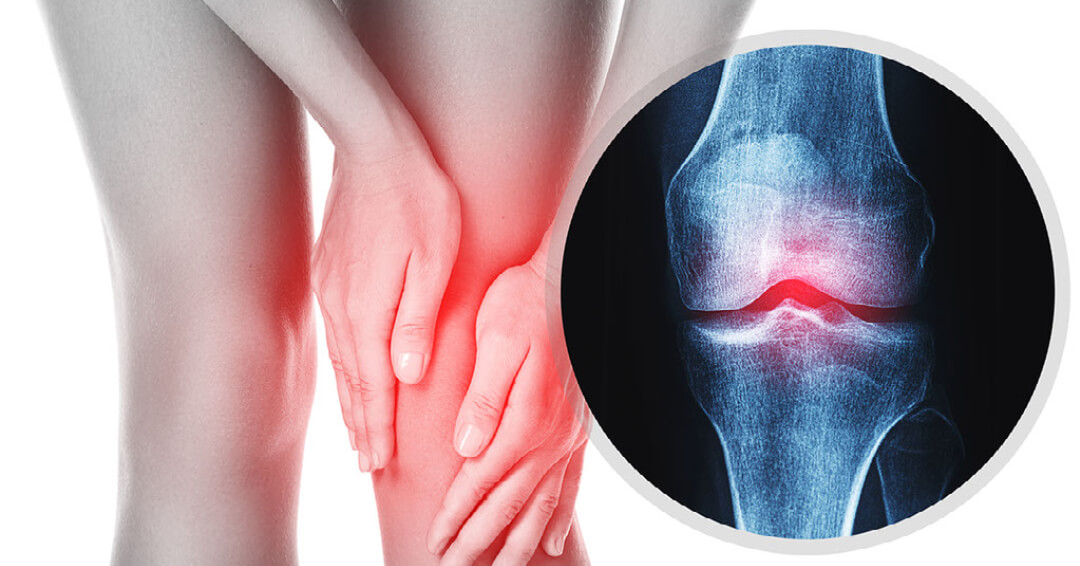

무릎관절염은 무릎에 염증이 생기고 관절이 손상돼 통증과 뻣뻣함이 나타나는 질환입니다. 무릎관절염은 크게 골관절염, 류마티스 관절염, 외상 후 관절염 등 3가지 유형이 있습니다.

골관절염은 무릎관절염의 가장 흔한 유형으로 관절을 완충하는 연골이 점진적으로 마모되면서 발생합니다. 이는 뼈가 서로 마찰되어 무릎 관절에 통증, 붓기, 뻣뻣함을 유발할 수 있습니다. 골관절염의 위험 요인으로는 나이, 비만, 유전, 관절 부상, 과용 등이 있습니다.

류마티스 관절염은 신체의 면역체계가 관절을 공격해 염증과 손상을 일으키는 자가면역질환입니다. 이는 무릎 관절에 통증, 붓기, 뻣뻣함, 변형을 초래할 수 있습니다. 류마티스 관절염의 위험요인으로는 유전, 흡연, 특정 바이러스나 박테리아에 대한 노출이 포함됩니다.

외상 후 관절염은 무릎 관절에 골절이나 인대 파열 등의 부상을 입은 후 발병하는 관절염의 일종입니다. 이는 무릎의 연골과 뼈에 손상을 일으켜 통증, 붓기, 뻣뻣함을 유발할 수 있습니다.